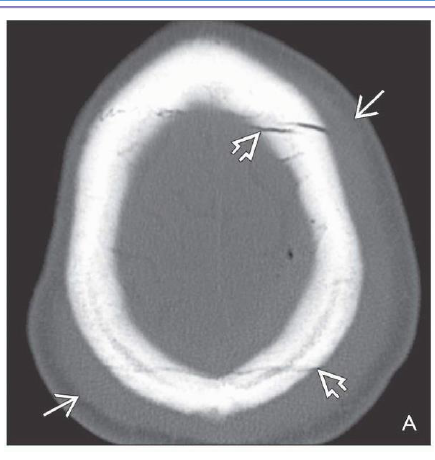

What is the dx?

Axial bone CT shows extensive subgaleal hematoma and linear skull fractures crossing the

sagittal suture.